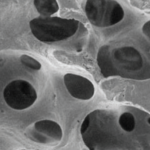

Lately, various surface treatment methods have been studied to facilitate rapid and strong osseointegration. According to the surface roughness and topography, the surface chemistry plays an important role for osseointegration. Titanium (Ti) and Ti alloys are bioinert surfaces and are not able to directly bond with bone. One method for increasing surface reactivity is to coat the Ti surface with nanostructured calcium. Many in vitro and in vivo studies have already reported the effectiveness of nanostructured calcium coating.

For example, in vitro studies have reported that surface modification using calcium ions increased the growth of osteoblastic cells and promoted the precipitation of apatite on Ti surfaces in simulated body fluid. Plus, the effects of cell adhesion to calcium-incorporated Ti surfaces were reduced in human alveolar bone cells and MG-63 cells, and increased in human osteoblasts. Several in vivo studies have reported that incorporating calcium into Ti implants by hydrothermal treatment stimulated osseointegration by increasing the BIC % when compared with untreated Ti implants in rabbit models.

1. Nano bone matrix layer of Ca2+ -incorporated S-L-A surface

Ca2+ is incorporated into the fixture structure to create a CaTiO3 nano-structure. This then forms a unique & uniform nano-structure with Ca2+ions, which activate osteoblasts in living organisms.